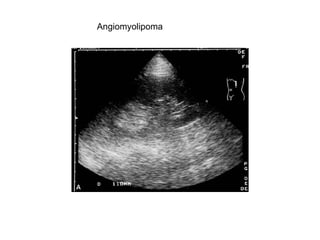

Angiomyolipoma